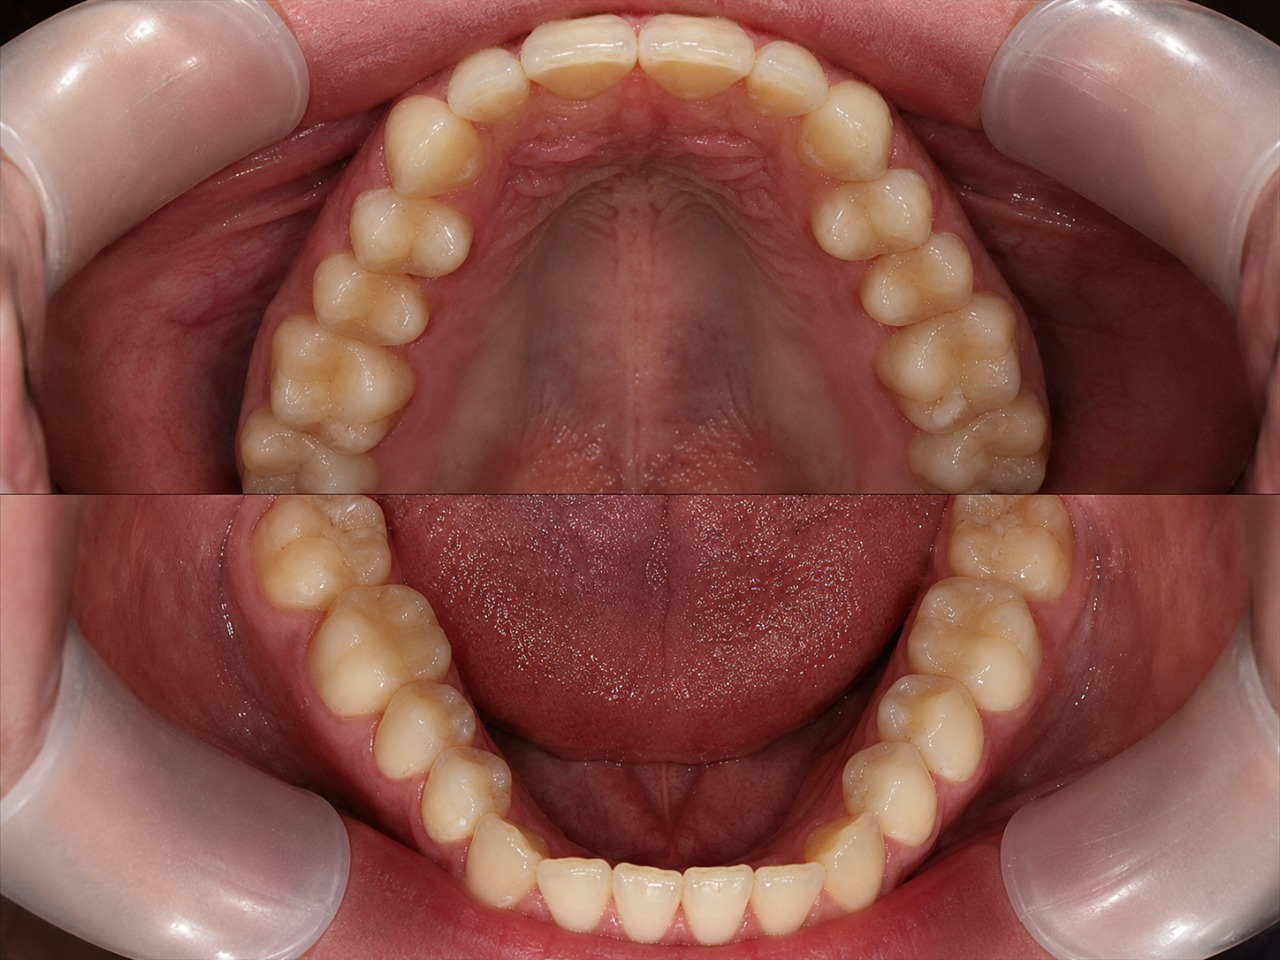

Перед началом лечения проводится диагностика.

Затем врач при помощи сканера снимает с зубов пациента

высокоточную 3D модель, и в специальной программе создает

компьютерную модель желаемой улыбки – именно так, как она

будет выглядеть после выравнивания прикуса. После этого

информация отправляется в лабораторию компании-производителя,

и он изготавливает индивидуальный комплект кап по модели.

- Перед началом лечения осуществляем максимально детальную диагностику на основании ТРГ снимков.

- С помощью специального программного обеспечения с математической точностью производим все рассчеты будущего лечения.